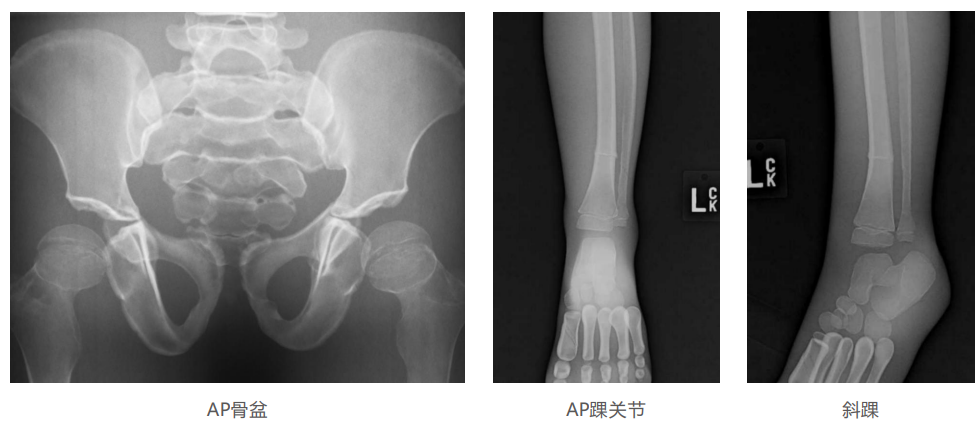

模体的大小和结构都代表了人体模体,使其便携和易于定位。包括头、胳膊和腿在内的整个身体。该系列包括六个部分的模体可单独或作为一个完整的集合。

右肢有伸直或弯曲两种配置。左臂和左腿可选伴有或不伴有内嵌骨折。

骨折版本包含最常见的人体骨折类型 ,包括胫骨扣带骨折和腓骨普通骨折;

第一跖骨骨折;桡骨切开复位骨折 ,第二中间趾骨常见骨折。组件由适当的聚氨酯和环氧材料制成,模拟人体组织的X射线衰减特性,用于诊断和治疗能量范围(50 keV - 25 MeV) 。 材料经久耐用 ,耐冲击,适合连续搬运。透明的软组织有助于解剖标志的视觉指示。

• 左附件五种最常见的骨折;